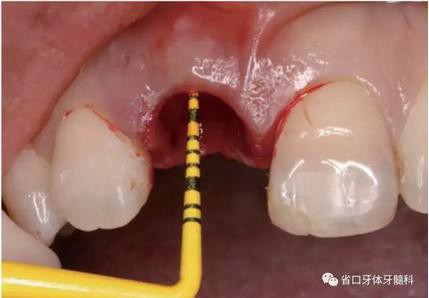

圖12 平行桿檢查

圖13 平行桿檢查

圖14 平行桿檢查

(1)微創(chuàng)拔牙及即刻種植:術(shù)前拍攝口內(nèi)照及實(shí)施牙周基礎(chǔ)治療。常 規(guī)消毒鋪巾阿替卡因局麻下微創(chuàng)拔除上頜右側(cè)中切牙,搔刮拔牙窩及根尖肉 芽組織。探測(cè)牙槽骨唇側(cè)骨壁及鄰面牙槽嵴完整,牙齦無(wú)撕裂。不翻瓣下于上頜右側(cè)中切牙缺隙近遠(yuǎn)中中點(diǎn)的腭側(cè)牙槽骨及根方定位,按照逐級(jí)預(yù)備的原則,緊貼牙槽窩腭側(cè)骨壁制備種植窩洞,植入Zimer®3.7mm×13mm TSV種植體1顆,植入扭矩>35N·cm,以O(shè)sstell測(cè)量種植體的ISQ值為68。 種植體平臺(tái)位于唇側(cè)齦緣中點(diǎn)下3mm,與唇側(cè)骨壁內(nèi)側(cè)面形成的跳躍間 隙約2mm,置入Bio-Oss®細(xì)顆粒骨粉0.25g,上愈合基臺(tái)關(guān)閉創(chuàng)口。術(shù)后 CBCT檢查顯示:種植體利用牙槽窩根方骨質(zhì)固位,緊貼牙槽窩腭側(cè)骨壁, 其唇側(cè)面與牙槽窩唇側(cè)骨壁的內(nèi)側(cè)面所形成的跳躍間隙(約2mm)可見(jiàn)顆 粒狀顯影物充填。牙槽窩的唇側(cè)骨壁及唇側(cè)倒凹無(wú)缺損穿孔。